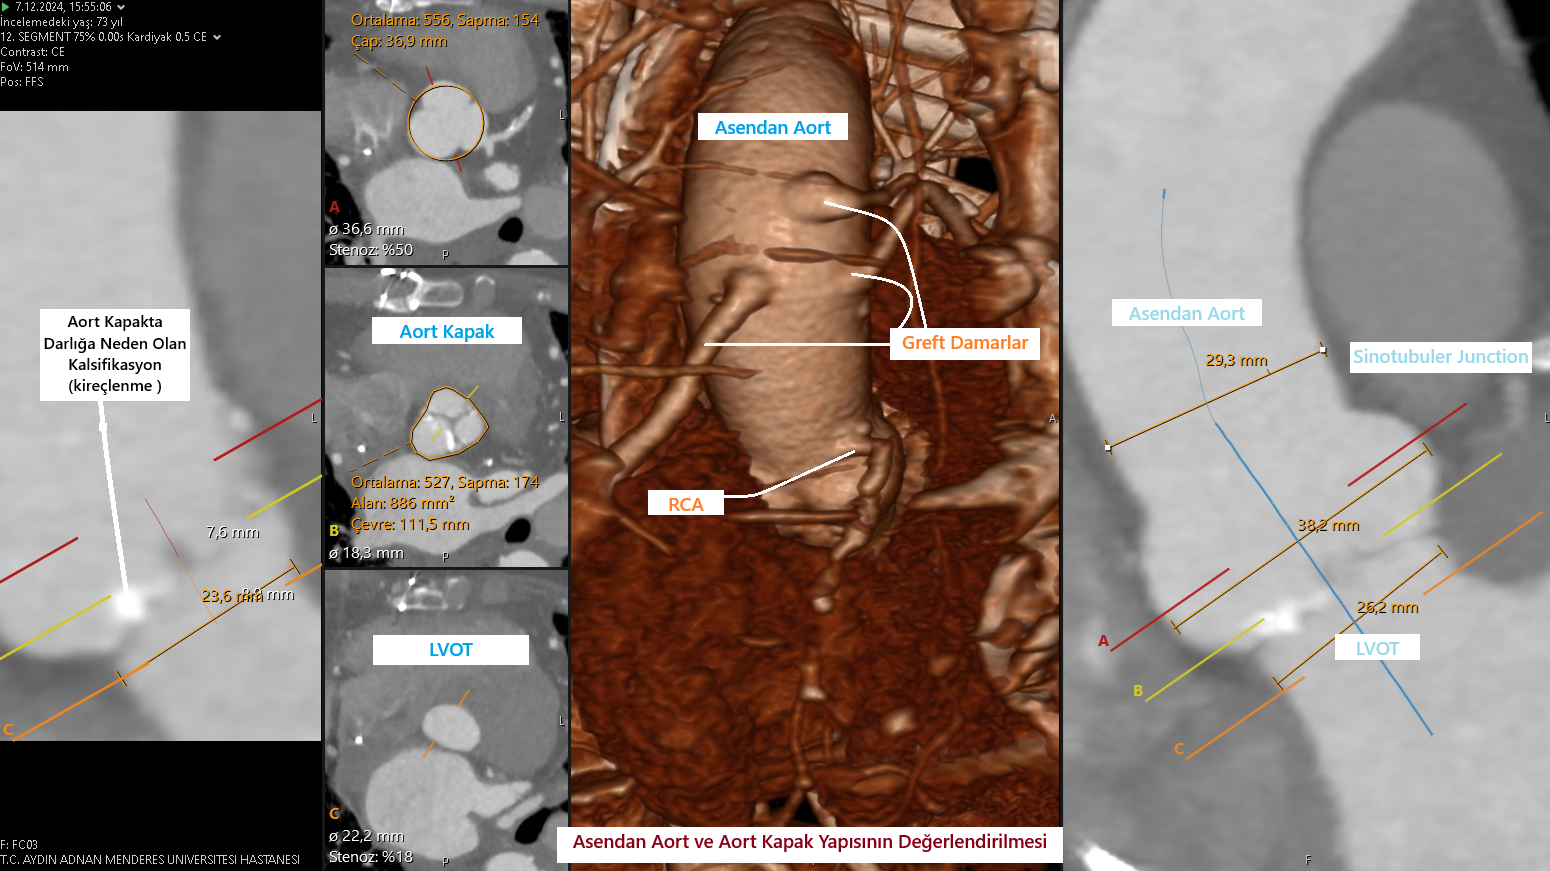

TAVI genellikle derin sedasyon ya da genel anestezi ile yapılan – kasıktaki atardamardan küçük bir kesi ile yapılan ağrısız bir işlemdir. Koroner anjiyografi veya stent işleminden kullanılan kateterlere benzeyen dar ve esnek bir tüp (katater)kasıkta bulunan atardamarınıza yerleştirilir ve kalbinizdeki aort kapağınıza ulaşılır. Bu kateter esnekliğini yitirmiş ve kireçli eski kapağınızın üstüne yedek bir kapak takmak için kullanılır. Bu katerterden geçen sistem ile ameliyata gerek kalmadan yeni biyoprotez kapak eskimiş kapağın üzerine yerleştirilir.

Resim 2: TAVİ' nin şematik görüntüsü.